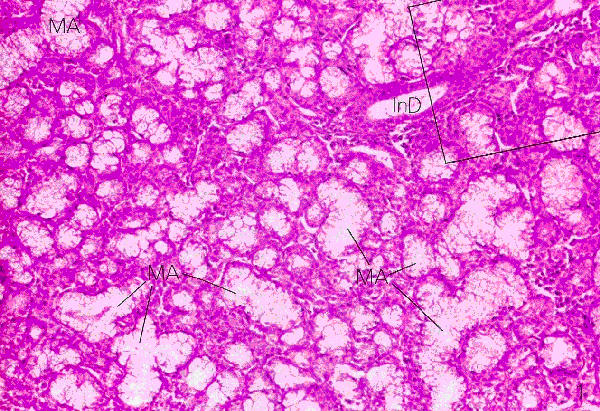

The Sublingual gland

• Does not contain a distinct connective tissue capsule, but prominent tissue septae are present in the gland

• This gland is a compound tubulo-alveolar gland with mixed secretory units:

1. 1. Serous secretory units - 20%

2. 2. Mucinous secretory units - 80% (also contains serous demilunes)

Plate 68 (Fig. 1)

Ross and Romrell p. 415

Mixed Secretory Units

• These units consists of serous and mucinous alveoli or a combination thereof mucinous-serous alveolus

• The latter consists of a mucinous alveolus with a serous demilune which secretes into the lumen of the mucinous alveolus via intercellular ductules

Plate 68 (Fig. 2)